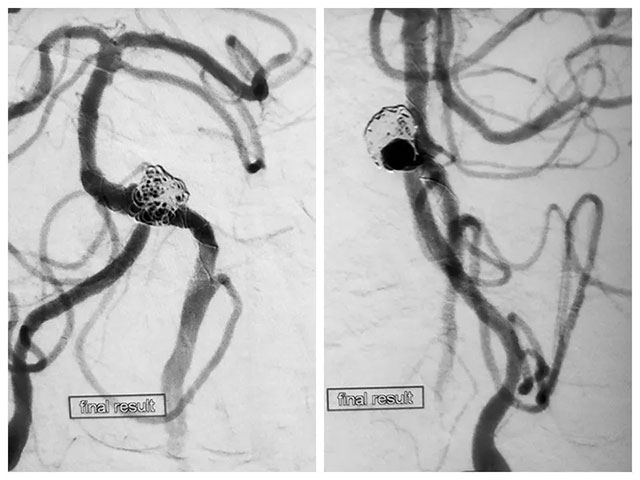

张琪博士在刘春医生、周林华医生协助下成功为患者进行了左侧椎动脉闭塞开通术、左侧椎动脉夹层动脉瘤支架辅助弹簧圈栓塞术。

先向瘤体内稀疏填入一枚弹簧圈,随后释放支架至覆盖瘤颈,随后通过支架网孔继续向瘤腔内填入数枚弹簧圈,再次造影见大部分瘤体不显影。但子瘤内仍可见少量血流,通过支架导管再次释放一枚支架覆盖瘤颈,再次造影后见动脉瘤无显影,撤出系统后行血管造影,未见血栓形成,CT检查无出血。

DSA造影手术、左侧椎动脉闭塞开通手术、支架辅助弹簧圈栓塞手术处理夹层动脉瘤和子瘤,这位病患先后进行了四次手术,历时近12小时,最终完成血管内重建性治疗。

▲ 术后造影